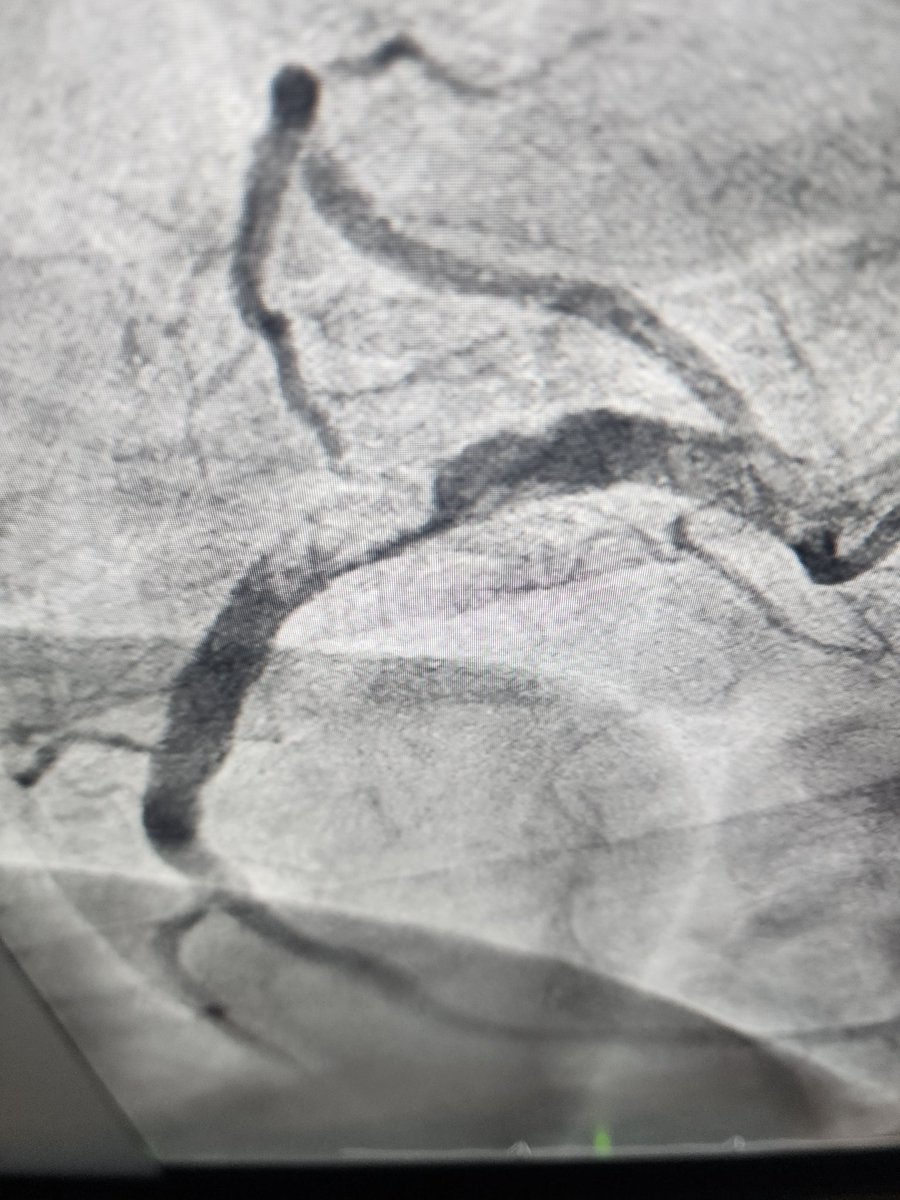

إستشاري وأستاذ أمراض القلب وقسطرة الشرايين والتصوير النووي بكلية الطب IMSIU للتواصلalnemerk@hotmail.com مستشفى الحمادي بالنزهة الرياض منسقة المواعيد 0538299999

مهمته في الحياة هي نشر المعرفة الطبية الدقيقة وعلاج المفاهيم الخاطئة حول صحة القلب والوقاية منه، مما يساهم في حياة أفضل وأكثر وعياً للمجتمع. يسعى لأن يكون مرجعاً موثوقاً ومصدر إلهام لتبني عادات صحية مستدامة بين المتابعين، مع الاستفادة من خبرته الأكاديمية السريرية. هدفه النهائي هو تقليل الأمراض القلبية من خلال التوعية الذكية والتواصل الفعال.